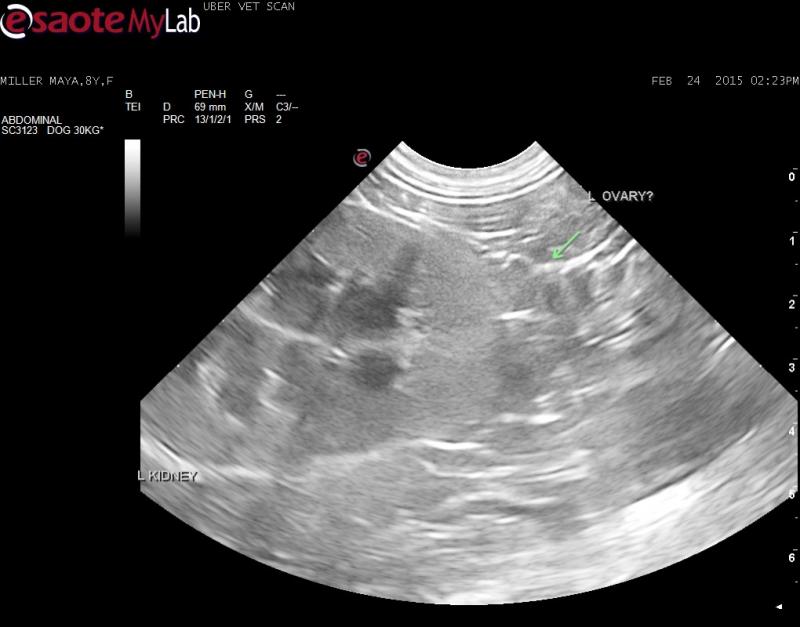

– I could not find a uterus or right ovary but found a structure caudal the left kidney that may be a left ovary?

What are your thoughts on the adrenal mass? Do you think the structure I am pointing to is a left ovary?

On the still I can’t really

On the still I can’t really comment one way or the other. Do you have a video of that region?